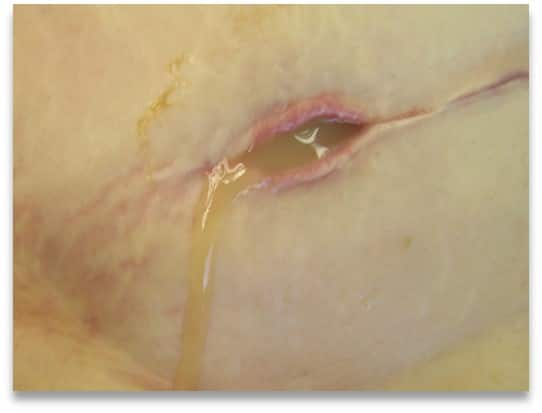

• the exudate, or fluid in the wound – its colour, consistency, odour and amount

If you notice that exudate is pooling, or if you believe that the exudate’s composition is preventing the wound from healing, your first priority should be to remove the excess exudate. Choosing the right wound dressing is the best way to do this. You can read more about how to do that here.

• exudate pooling, leakage and soiling1, 3

The following chart describes the different types of exudate. The wound’s exudate gives you important information about the wound’s health. If you notice an unexpected change in exudate characteristics, this may mean that there is a change in the wound’s status, e.g that the wound is infected. If this happens, you should re-evaluate the wound as quickly as possible.4, 3